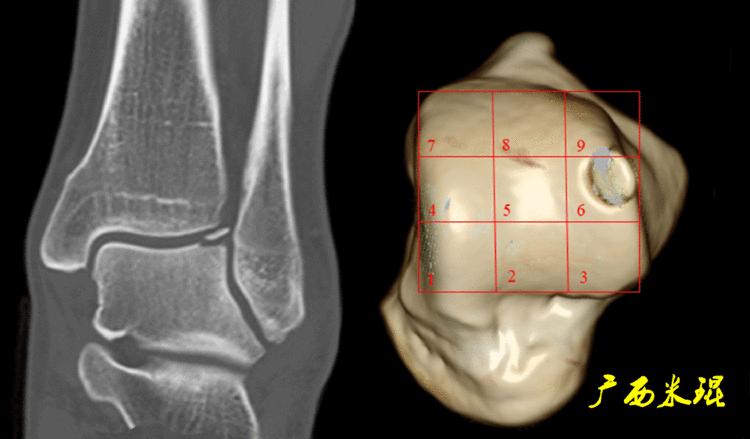

(2)CT检查

CT检查相对于X线检查而言更细致,但没有MR敏感,如果仅仅是软骨的病损,CT也容易漏诊。

即使这样,CT检查能够进行三维成像,可以更加直观的显示软骨剥脱的具体情况,这可是其他检查无法实现的。

Raikin将距骨骨软骨进行九宫格分区对临床是很有帮助的,距骨骨软骨的后内侧损伤一般发生在4区和7区,前外侧损伤一般发生在3区和6区。除此之外,Raikin九宫格分区对手术也有很大帮助,4、5、6区的损伤手术显露有一定的困难,如果选择骨软骨移植一般都需要采取截骨显露的方法。